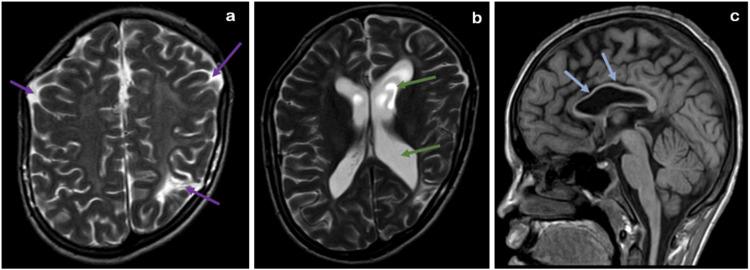

Spinal dysraphism is a spectrum of congenital anomalies caused by incomplete neural tube closure during early development, leading to spine and spinal cord defects. These can be broadly categorized into anomalies of gastrulation (including disorders of notochord formation and integration), anomalies of primary neurulation (such as premature disjunction and nondisjunction), combined anomalies of gastrulation and primary neurulation, and anomalies of secondary neurulation. This case report focuses on a 15-year-old male patient who exhibits a range of congenital spinal anomalies of spinal dysraphism spectrum, each contributing to a complex clinical picture. The primary aim of this report is to highlight the critical role of multimodal imaging in the evaluation of such conditions. Detailed imaging studies, particularly magnetic resonance imaging (MRI), are indispensable in accurately diagnosing, guiding surgical planning, and managing the diverse anomalies associated with spinal dysraphism. In this case, imaging findings were pivotal in identifying multiple congenital abnormalities, including scoliosis, butterfly vertebrae, block vertebrae, spina bifida occulta, and diastematomyelia. These conditions pose significant diagnostic and management challenges due to their varied presentations and complications.

脊柱裂是一组先天性异常疾病,由早期发育过程中神经管闭合不全引起,导致脊柱和脊髓缺陷。这些异常可大致分为原肠胚形成异常(包括脊索形成和整合障碍)、原发性神经管形成异常(如过早分离和不分离)、原肠胚形成和原发性神经管形成联合异常以及继发性神经管形成异常。本病例报告聚焦于一名15岁男性患者,他表现出一系列脊柱裂谱系的先天性脊柱异常,每种异常都导致了复杂的临床表现。本报告的主要目的是强调多模态成像在评估此类病症中的关键作用。详细的影像学检查,尤其是磁共振成像(MRI),对于准确诊断、指导手术规划以及管理与脊柱裂相关的各种异常至关重要。在本病例中,影像学检查结果对于识别多种先天性异常至关重要,包括脊柱侧弯、蝴蝶椎、融合椎、隐性脊柱裂和脊髓纵裂。由于这些病症表现多样且并发症复杂,给诊断和治疗带来了重大挑战。